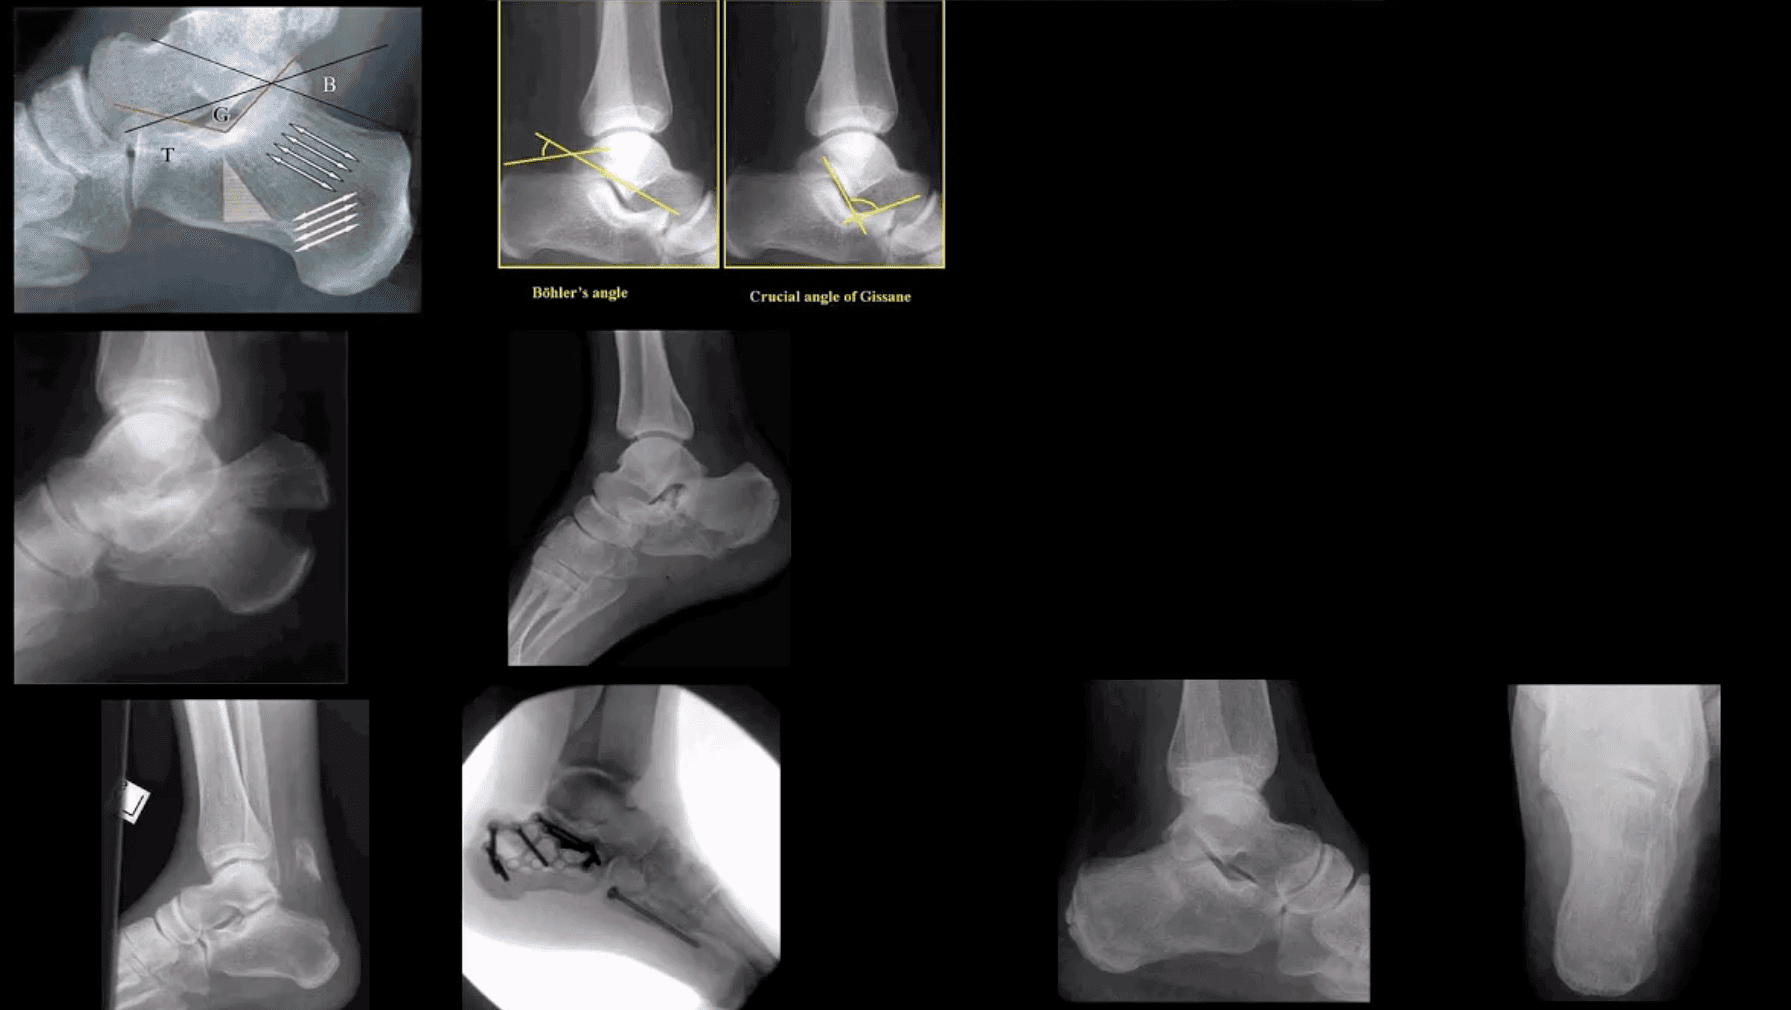

Calcaneal Fracture

- Most frequent tarsal Fx. 17% open Fx

- Mechanisms: axial loading (intra-articular Fx into sub-talar and calcaneal-cuboid joints in 75% cases). Avulsion by Achilles tendon (m/c in osteoporotic bone). Stress (fatigue) Fx.

- Intra-articular Fx carries a poor prognosis. Typically comminuted. Rx: operative.

- B/I calcaneal intra-articular fx with associated vertebra compression Fx with associated vertebral compression Fx (T10-L2) often termed Casanova aka Don Juan (Lover’s) fx.

- Imaging: x-radiography with added “heel view” 1st step. CT scanning is best for Dx and pre-op planning.

- Radiography: Bohler’s angle (<20-degrees) Gissane angle >130-degrees. Indicate Calcan, Fx.